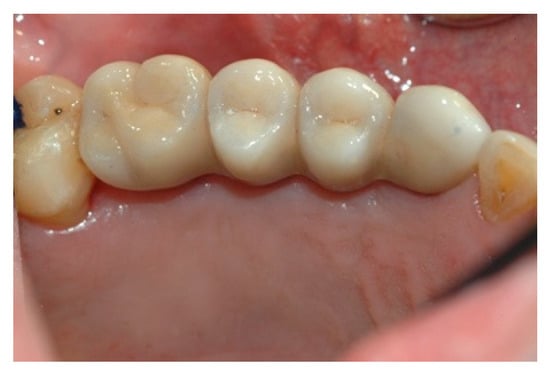

When the prosthesis was positioned, the mesostructure was fixed by tightening the screws with a torque wrench at 30 Ncm, and the superstructure was cemented by carrying out a radiographic check to evaluate the structural coherence (Figure 12, Figure 13 and Figure 14).

Figure 12. Cementing the superstructure.

Prosthesis 02 00023 g012

Figure 13. Cementing the superstructure.